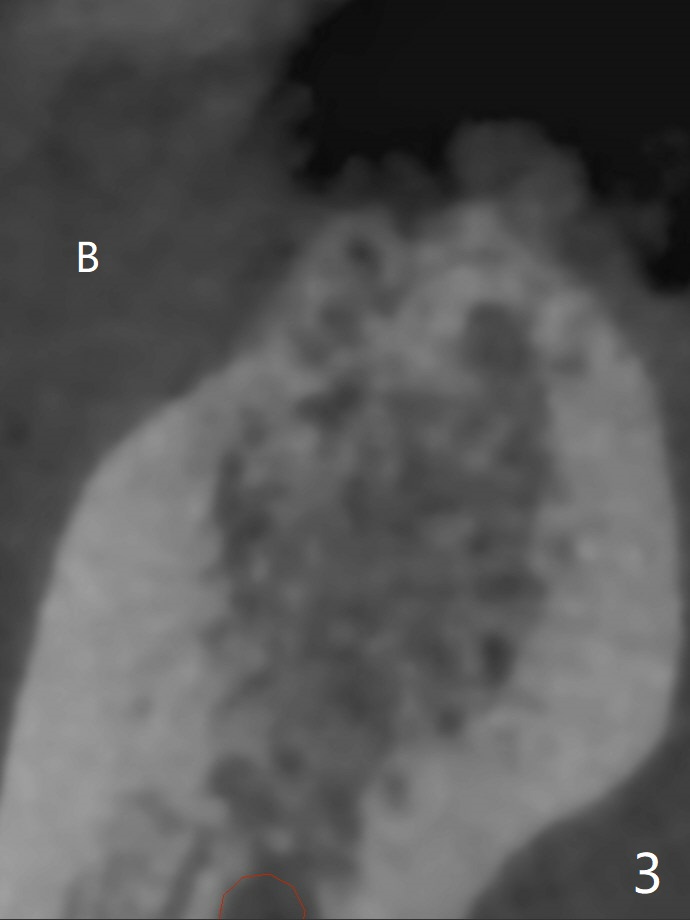

A 46-year-old woman returns for preparation for an implant at #30 two years 3 months post #6 (M) and 7 implant crown cementation (Fig.1). With the moderate ridge, implant placement should be easy, but the vertical restorative height is limited due to the opposing supraerupted molar. If the keratinized gingiva is narrow, make incision instead of tissue punch. In fact the crestal cortex is the most important structure associated with implant placement and should be carefully studied prior to implant design (Fig.2 arrowheads in 3D view as well as the sagittal and coronal (Fig.3) sections). If socket preservation were done, the ridge would be wider and taller (Fig.4 yellow dashed line) with possible thicker cortical bone.